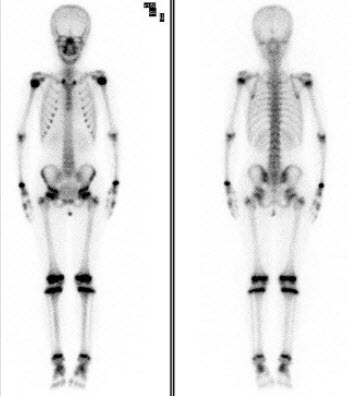

85、单项选择题

女,12岁,诉右下肢疼痛1周,体检无肿块,行全身骨显像如图,可能的诊断是()

A.大致正常的骨影像

B.右股骨远端骨肉瘤征象

C.右股骨骨髓炎

D.右下肢软组织蜂窝炎

E.右股骨头缺血坏死